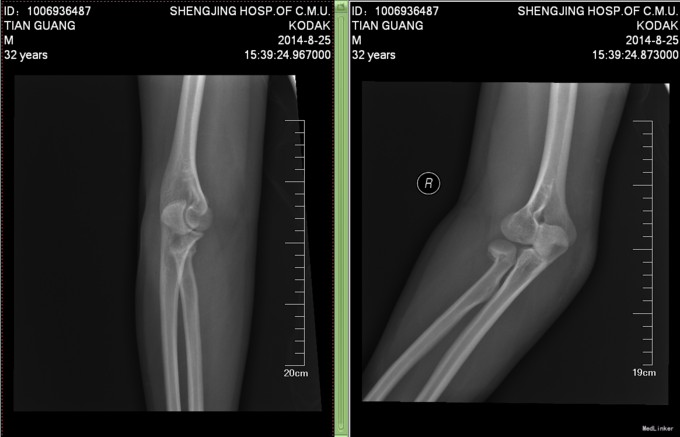

患者6小时前不慎摔倒,右手着地,当时即感右肘部剧烈疼痛,活动受限,被家人急送往奉天医院急诊,拍片检查示:右桡骨近端骨折,以“右桡骨骨折”收入院,现为进一步诊治,来我院就诊,以“右桡骨骨折”收入院,患者病来无头晕头痛,无恶心呕吐,无咳嗽咳痰,无发热寒战,饮食睡眠正常,二便正常,体重无明显减轻。

患者平车推入病房,右上肢甲板固定中,右肘部疼痛,压痛(+),可触及骨擦音,骨擦感,无明显淤血瘀斑,患肢末端血运可,右上肢皮肤感觉较健侧无明显异常,手指可活动,右桡动脉可触及搏动。